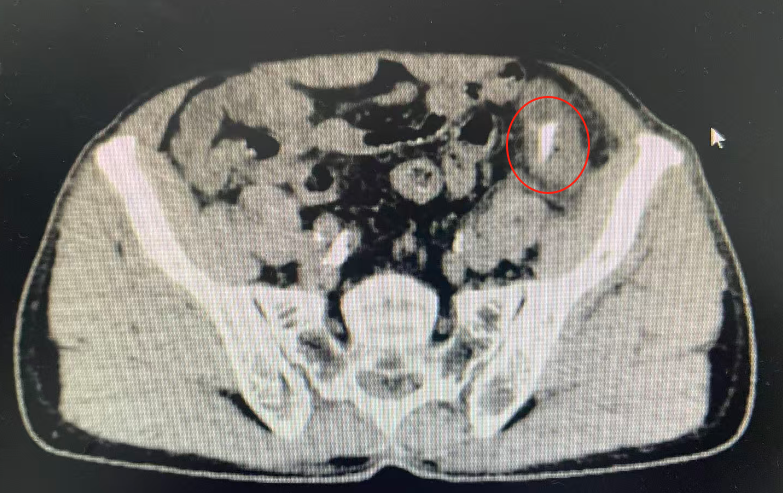

8月15日,该患者因持续加重的左下腹胀痛,来到我院消化内科就诊。接诊的张绍珠副主任医师详细询问病史并进行了仔细的查体,结合腹部影像学结果,敏锐地判断出患者存在肠穿孔可能,病情危急!

消化内科立即发出会诊邀请,外科任培土主任及杨京茹副主任迅速响应,评估病情,考虑患者乙状结肠穿孔、急性弥漫性腹膜炎,决定立即进行手术探查。医院为其开启绿色通道,启动紧急手术预案,并于当日中午由杨京茹副主任主刀,为患者施行了腹腔镜下乙状结肠切开异物取出联合乙状结肠修补术。

无影灯下,一场“缉凶”战迅速展开。在麻醉科周金萍主任团队实施的麻醉与全程监护下,手术顺利开展。术中探查发现,在患者乙状结肠中段,一根尖锐的鱼刺已完全刺透肠壁,腹盆腔有大量粪水,导致了严重的肠穿孔和腹腔感染。

杨京茹副主任随即带领团队展开精细操作:腹腔镜下顺利取出异物,见异物为一根锐利的鱼刺,长约3cm,修补穿孔肠壁,并进行了彻底的腹腔冲洗。整个手术过程一气呵成,患者生命体征平稳。